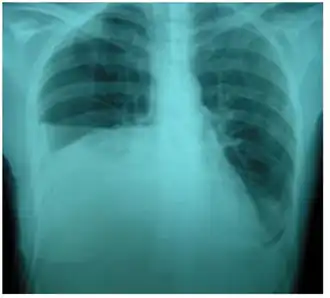

Derrame pleural no lado direito causado por urinotórax

Radiografia de tórax mostrando o urinotórax desaparecendo após o tratamento

O tratamento consiste principalmente em tratar o distúrbio subjacente do trato geniturinário.[6] Requer uma equipe multidisciplinar que inclui um pneumologista e urologista. Um tubo de nefrostomia ou cateter de Foley podem ser usados para aliviar qualquer obstrução subjacente. Quaisquer ferimentos são reparados.[11] Quando o distúrbio subjacente é tratado, o urinotórax se resolve rapidamente. Cirurgia torácica geralmente não é necessária,[3] especialmente se os sintomas respiratórios forem mínimos ou inexistentes.[6] Pleurodese também é ineficaz.[11]